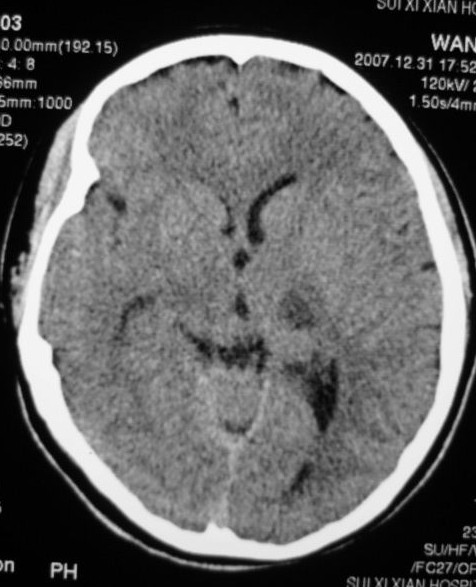

以下是引用zjzjr在2008-2-19 15:45:00的发言:[br]左侧小脑缺血性脑梗塞,基底节区脑梗塞,强烈建议血管造影,除外烟雾病。

以下是引用玉真在2008-2-19 17:46:00的发言:[br]多发性脑梗塞,不知病人是否有风心或先心病史